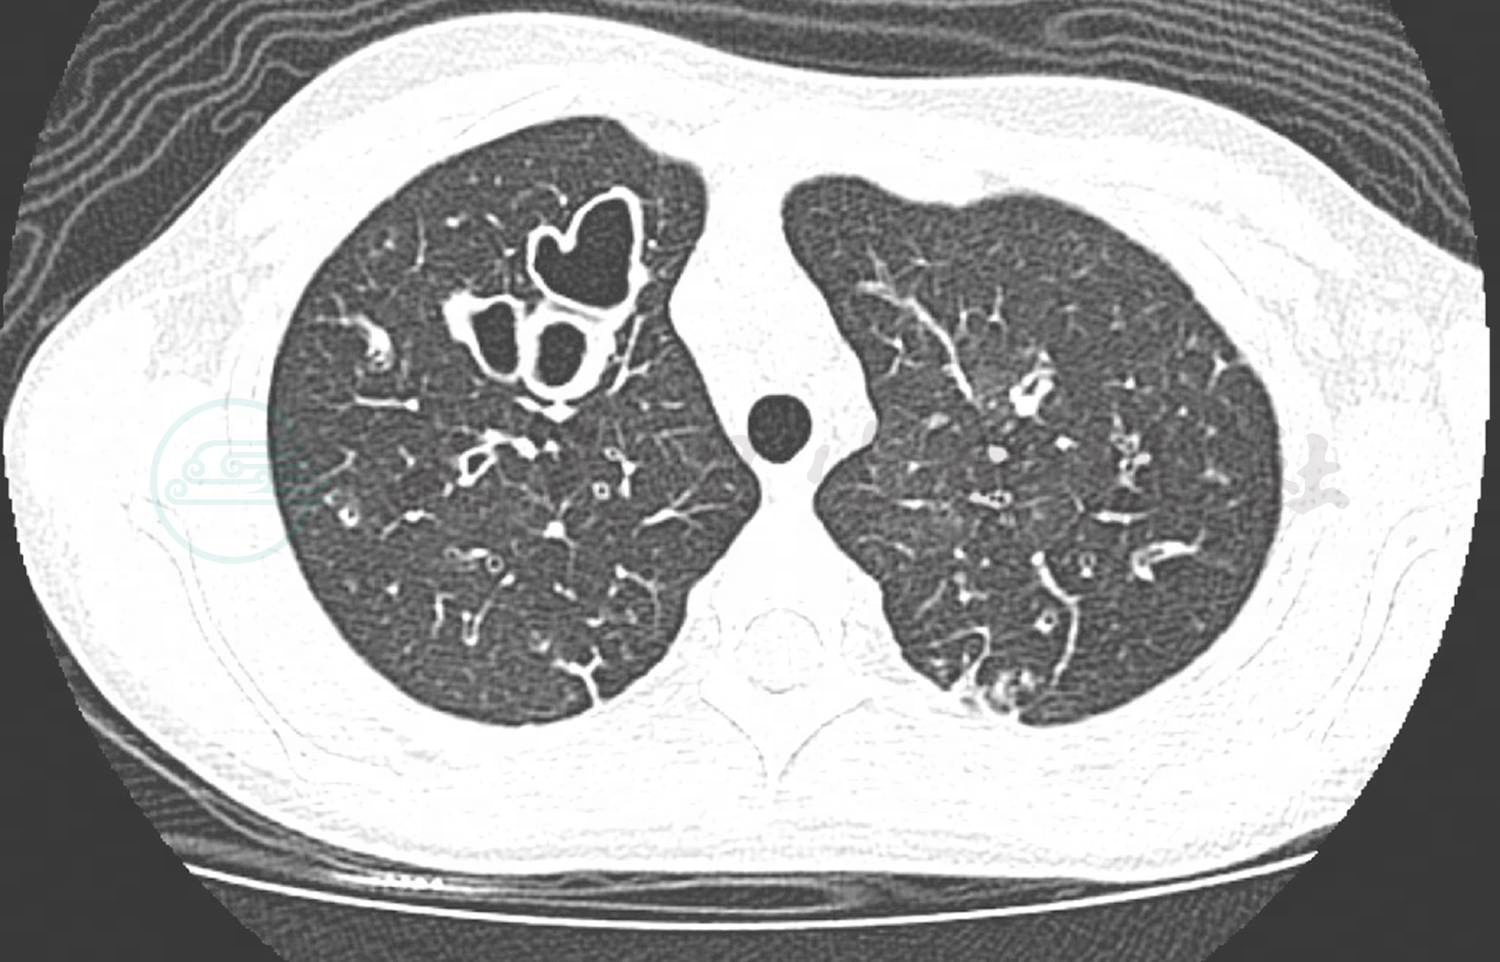

入院后完善实验室检查。血常规:C反应蛋白 14mg/L;WBC 13.0×109/L;LY% 20.2%;NE% 74.2%;HB 132.0g/L;BPC 303×109/L;ESR 49mm/h;PCT 0.12ng/ml。炎症指标表明白细胞轻度增高,以中性粒细胞为主,血沉明显增快,结合患儿慢性长期咳脓痰病史,首先考虑细菌感染。结合痰培养及肺泡灌洗液培养均提示铜绿假单胞菌优势生长。胸部CT检查(图1)提示两侧支扩伴感染、纤维灶形成,纵隔淋巴结增大,影像学证实存在支气管扩张表现。铜绿假单胞菌确实为支气管扩张合并感染的主要常见致病菌。根据药敏的结果,予以头孢他啶静滴抗感染治疗,同时予以乙酰半胱氨酸雾化吸入对症处理,辅以拍背、体位引流等物理治疗。同时完善鼻窦CT检查,提示存在全副鼻窦炎,根据耳鼻咽喉科会诊意见,予以局部用药对症处理。结核斑点试验结果阴性。肺功能:最大肺活量1.93L,占预计值的80.6%,正常。用力肺活量1.93L,占预计值的82.9%,正常。一秒量(FEV1)1.25L,占预计值的63.7%,轻度下降。一秒率(FEV1/VCMAX)64.44%,轻度下降。呼气流速各峰值(FEF25/50/75):轻至重度下降。气管镜下纤毛活检电镜检查提示纤毛结构正常。体液免疫检查发现 IgG 15.20g/L,IgA 4.38g/L,IgM 1.43g/L,总IgE 85.40U/ml,均正常;T细胞亚群提示NK细胞25.19%,CD3+% 62.43%,CD3+/CD4+ 29.10%,CD3+/CD8+ 23.70%,CD3-/CD19+11.11%,CD4+/CD8+ 1.23,均在正常范围,常见的体液或细胞免疫功能缺陷依据不足。考虑患儿存在支气管扩张及慢性鼻窦炎,为鉴别Kartagener综合征,明确是否存在内脏反位,予以完善腹部B超检查。腹部B超检查提示存在肝脏弥漫性病变。进一步完善腹部CT提示脾脏稍大,肝脏表面不均匀,门静脉较宽,下腔静脉较宽。心脏超声及肝功能指标正常。综合上述检查及相关病史,患儿既往不存在重症肺炎的病史,无法用单纯的既往感染因素解释目前存在的弥漫性的支气管扩张;实验室检查排除常见的免疫缺陷;影像学检查排除支气管异物;纤毛活检排除原发性纤毛不动综合征;不存在内脏反位,Kartagener综合征的诊断依据不足。但是患儿存在肝脏病变,考虑患儿的支气管扩张存在隐藏的基础疾病,现有的实验室检查无法探寻到病因。根据现有情况,与家长沟通后进行全基因测序检查以进一步明确诊断。经过抗感染治疗,入院第4天患儿咳嗽好转,入院第6天痰量明显减少,入院第12天咳嗽明显减少和肺部啰音消失,予以出院。予以小剂量红霉素,吸入用乙酰半胱氨酸及泛福舒免疫调节剂治疗并临床随访。

图1 两侧支气管扩张伴感染、纤维灶形成,纵隔淋巴结增大